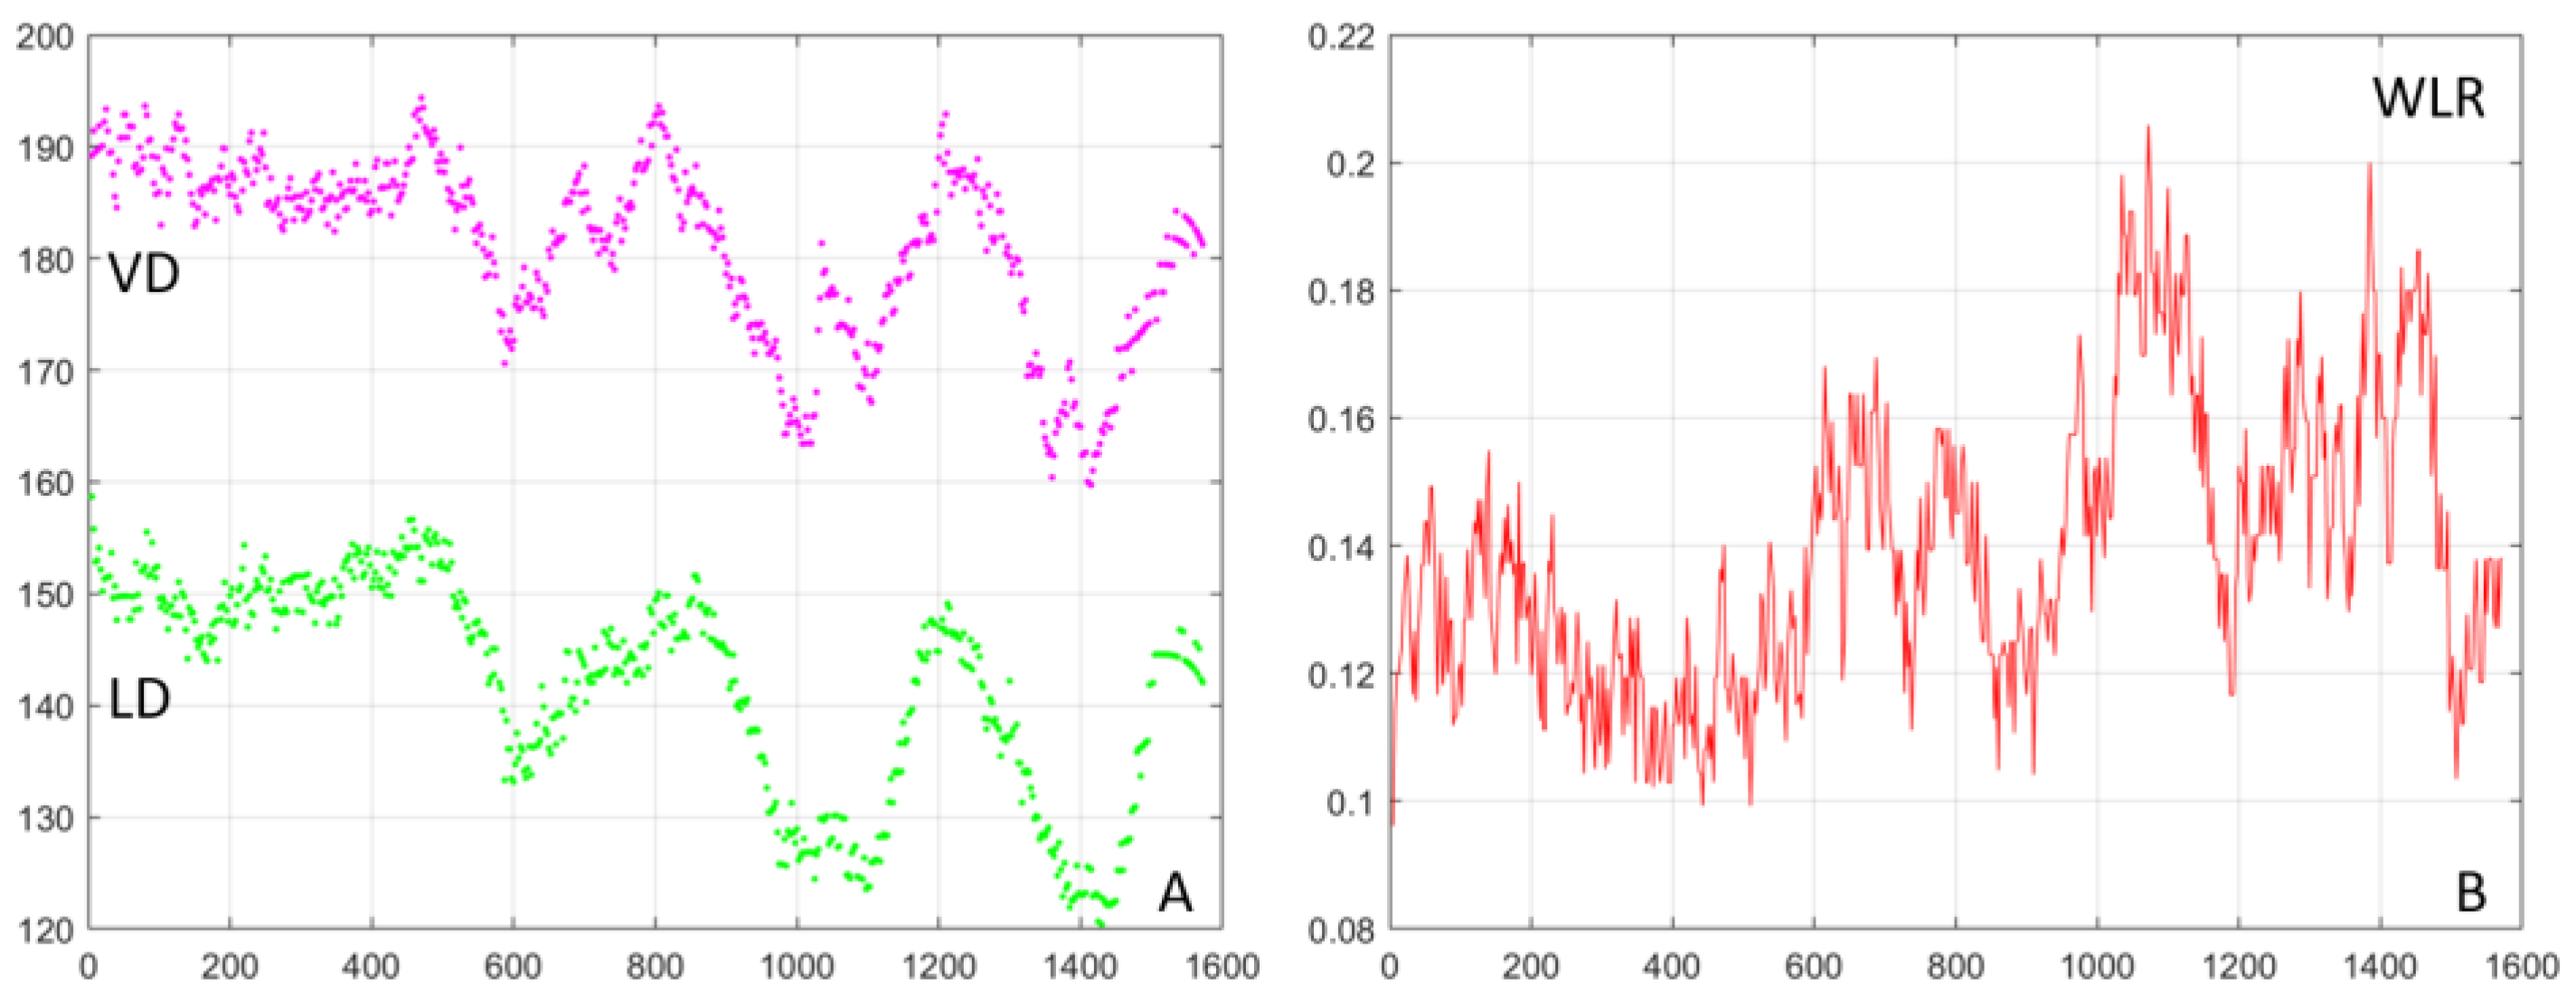

3. Results